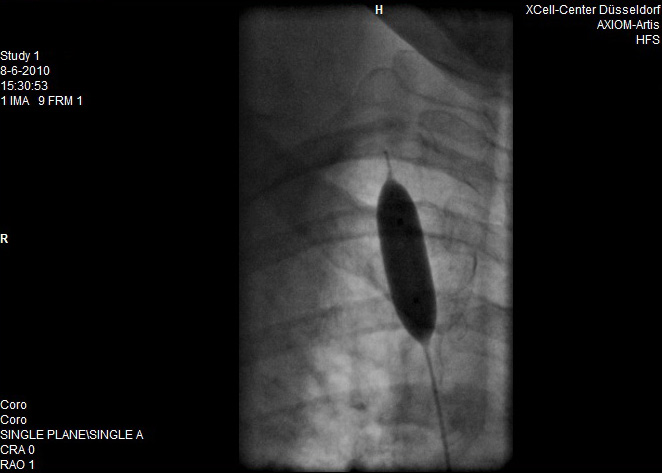

En hier de scans van de behandeling

Opmerkingen bij bestand: Dit is voor de behandeling

voor.jpg

voor.jpg [ 47.48 KiB | 19706 keer bekeken ]